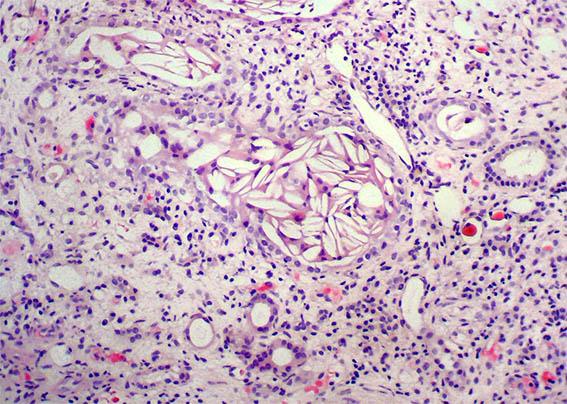

Figure 4. H&E, X100.

Figure 5. Masson's trichrome stain, X100. Observe what is in some tubules, which are very dilated.